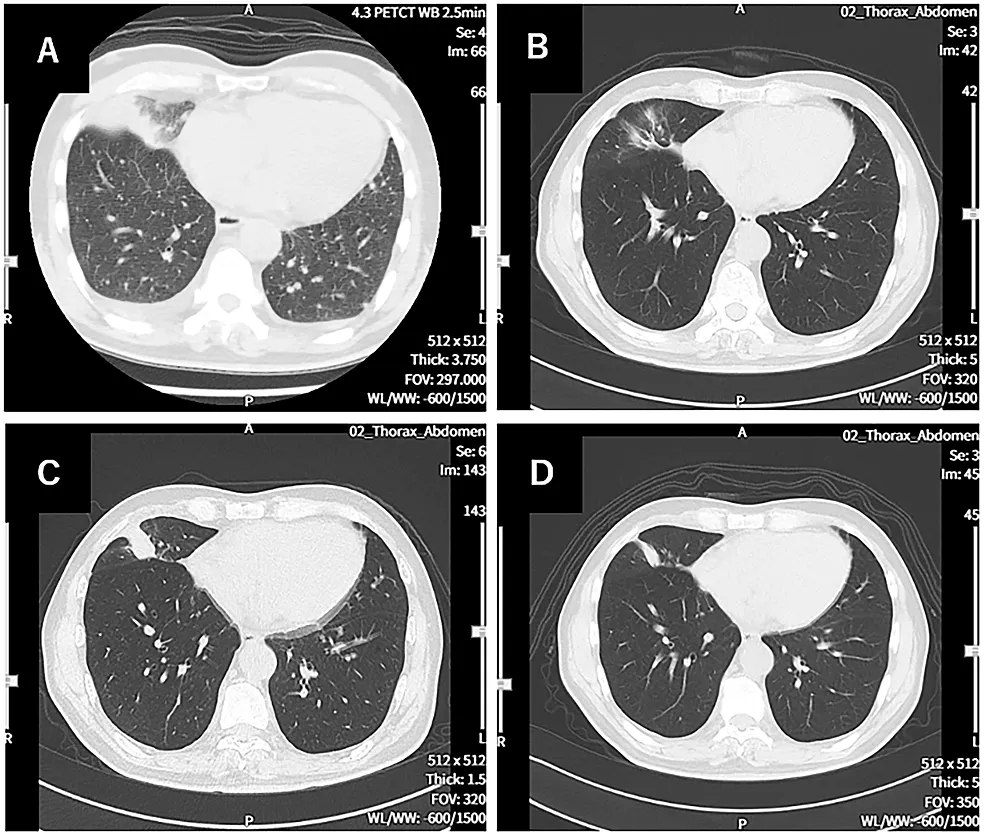

1.与治疗开始时(第0天)的胸部CT相比,第114天的胸部CT观察到癌症明显缩小(图1)。

图1 胸部CT图象对比

A:诊断时的CT图像。可见左右胸腔积液,以及原发性右下肺癌。B:第114天的CT图像。原发病灶几乎消失。C:第213天的CT图像。显示原发病变复发。D:第338天的CT图像。原发复发病灶已缩小。